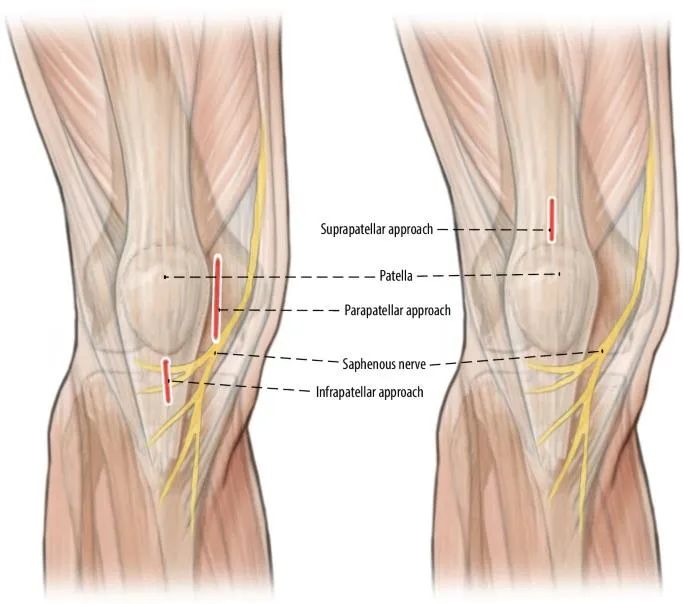

La principale cause de désalignement dans les fractures tibiales proximales est la déformation causée par la traction du tendon du quadriceps lors de la flexion du genou et le conflit mécanique entre la pointe de l'ongle et le cortex tibial postérieur lors de l'insertion de l'implant.La rotule empêche également l'entrée axiale du clou dans le plan sagittal (Fig. 1a, b).Par conséquent, une autre méthode courante d'accès au point consiste à effectuer une incision parapatellaire médiale, qui conduit à une légère insertion médiale à latérale du clou (Figs. 1c et 2).Lorsque le clou pénètre dans le canal intramédullaire en aval de la fracture, la partie proximale s'incline en valgus (Figure 2).Enfin, la tension de repos des muscles de la loge antérieure contribue légèrement au valgus (Figure 3).

Figure 1 a,b En utilisant l'approche infrapatellaire conventionnelle, la rotule empêche l'entrée axiale du clou, ce qui entraîne la déformation courante de l'alignement sagittal apical antérieur et de l'alignement coronal en valgus.c Utilisation de l'approche parapatellaire pour l'alignement du clou centromédullaire.

L'épinglage du tibia dans une position plus étendue permet d'éviter les complications associées à une flexion peropératoire sévère du genou.la technique a été décrite par Gelbke, Jakma et al.en 2010 et est devenu de plus en plus populaire ces dernières années car l'épinglage du tibia dans une position de membre presque droite simplifie la manipulation et le repositionnement de la fracture.La fluoroscopie est devenue techniquement plus facile à réaliser.Les temps de fluoroscopie pour l'enclouage suprapatellaire ont été rapportés comme étant significativement plus courts que pour l'enclouage sous-patellaire.De plus, l'angle d'insertion du clou (dans le plan sagittal) est plus parallèle à l'axe longitudinal du tibia dans cette voie d'abord que dans le clou sous-patellaire ;cela évite les conflits mécaniques entre la pointe de l'ongle et la corticale postérieure, facilitant ainsi la réduction de la fracture.

La douleur antérieure du genou postopératoire est un problème connexe.Des douleurs antérieures au genou ont été signalées chez 50 à 70 % des patients ayant subi une fracture, seuls 30 % des patients ayant ressenti un soulagement de la douleur après le retrait de la plante interne.On estime que la formation de cicatrice associée à l'accès au tendon rotulien et au coussinet adipeux de Hoffa est une source potentielle de douleur postopératoire au genou.De plus, l'abord suprapatellaire évite l'incision traditionnelle de la branche de la branche rotulienne du nerf saphène, évitant ainsi l'engourdissement antérieur du genou et la lourdeur sensorielle (Figure 4).Le passage du clou à travers le tendon du quadriceps, laissant ainsi le tendon rotulien intact, semble réduire significativement le taux de douleur postopératoire au genou.